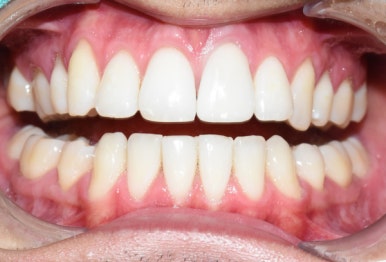

치료전후 사진

위 앞니 변색 치아 하나 치료 전(왼)-치료 후(오른쪽 사진)

다행히 처음 끼워드린 크라운에 환자분이 색상이나 모양 매우 만족하셔서

크라운을 다시 수정보내는 일 없이 한번에 장착하였습니다.

환자분이 매우 만족하셔서 뿌듯한 케이스 였습니다.